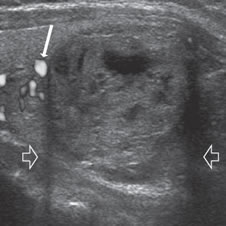

Un nódulo que tiene un componente quístico significativo, usualmente es un nódulo benigno hiperplástico, que ha acumulado abundante coloide (Figura 2a) o bien, un nódulo sólido que ha experimentado un proceso de degeneración colicuativa o hemorragia (Figura 2b). El coloide o el contenido líquido de un nódulo se ve anecogénico (negro en la imagen ecográfica) y las estructuras sólidas se ven ecogénicas (distintos tonos de grises), siendo la ecogenicidad similar al del parénquima tiroideo. En un nódulo sólido la ecoestructura y la ecogenicidad pueden ser variables. En general, la frecuencia de carcinoma es muy baja en nódulos quísticos13 y la mayoría de los carcinomas se presentan como nódulos sólidos (Figura 2c).

Figura 2. a) Quiste coloideo anecogénico y focos ecogénicos (flecha) con artefacto en cola de cometa; b) Nódulo mixto sólido-quístico (cabezas de flechas). Imagen vegetante (flecha) adherida a un tabique que se proyecta al lumen; c) Comparación entre el aspecto ecográfico de un cáncer papilar sólido (flecha abierta) y un quiste coloideo anecogénico.